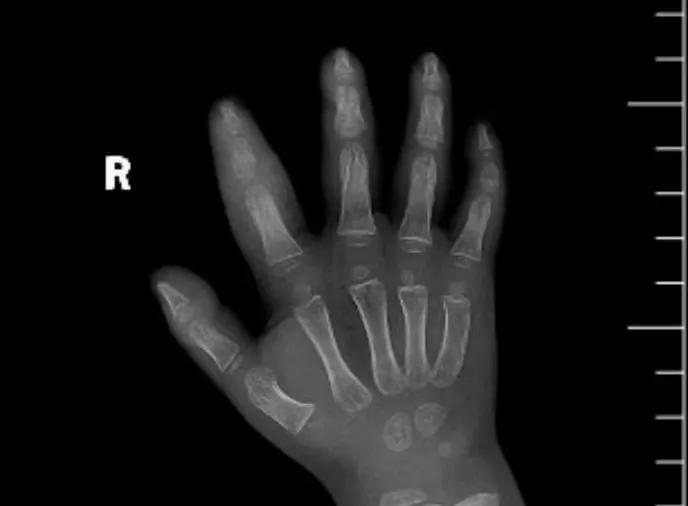

近日,市二院顯微外科接診一名3歲半的小患者,被玉米葉割傷右食指,因家長(zhǎng)疏忽大意,導(dǎo)致一個(gè)小小的傷口竟然發(fā)展成了骨髓炎。來(lái)院時(shí)患兒右食指腫脹明顯,既不能伸也不能彎,皮膚發(fā)燙,疼得哇哇大哭。

第三天開始,月月哭鬧不止,一直說(shuō)手疼,怎么哄也不行,于是在當(dāng)?shù)蒯t(yī)院治療了10來(lái)天,然而月月的手指依然腫得像個(gè)胡蘿卜,疼痛感依然存在。此時(shí),月月的媽媽才覺得事情不大對(duì)勁,于是經(jīng)過(guò)打聽,慕名來(lái)到市二院顯微外科。入院后,經(jīng)檢查發(fā)現(xiàn),月月的右食指骨質(zhì)有侵蝕,骨骺有缺損,甚至?xí)绊懸院笫种傅陌l(fā)育。聽到這個(gè)消息,月月媽媽感覺心都揪住了。

隨后,經(jīng)顯微外科團(tuán)隊(duì)充分的討論,制定了科學(xué)細(xì)致的治療方案,為月月做了感染灶清除及手指的開放引流,并留取了標(biāo)本做細(xì)菌培養(yǎng),為進(jìn)一步的合理用藥提供依據(jù)。經(jīng)過(guò)兩周的治療,月月的手指終于順利消腫愈合,并且手指功能活動(dòng)良好。說(shuō)起這一個(gè)多月的煎熬,月月媽媽不禁落淚,但總算是治愈了,笑容又重新回到她們一家的臉上。